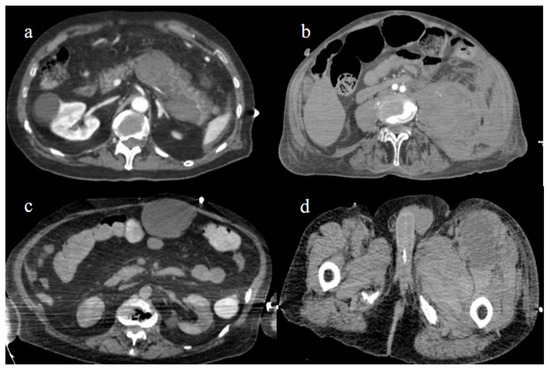

4.1. Small Bowel Ischemia and Ischemic Colitis

4.2. Splenic and Renal Infarction

4.3. Hemorrhagic Abdominal Complications

- Bonaffini, P.A.; Franco, P.N.; Bonanomi, A.; Giaccherini, C.; Valle, C.; Marra, P.; Norsa, L.; Marchetti, M.; Falanga, A.; Sironi, S. Ischemic and hemorrhagic abdominal complications in COVID-19 patients: Experience from the first Italian wave. Eur. J. Med. Res. 2022, 27, 1–9. [Google Scholar] [CrossRef]

- Peshevska-Sekulovska, M.; Boeva, I.; Sekulovski, M.; Zashev, M.; Peruhova, M. Gastrointestinal Ischemia—Stumbling Stone in COVID-19 Patients. Gastroenterol. Insights 2022, 13, 206–217. [Google Scholar] [CrossRef]

- Norsa, L.; Bonaffini, P.A.; Caldato, M.; Bonifacio, C.; Sonzogni, A.; Indriolo, A.; Valle, C.; Furfaro, F.; Bonanomi, A.; Franco, P.N.; et al. Intestinal ischemic manifestations of SARS-CoV-2: Results from the ABDOCOVID multicentre study. World J. Gastroenterol. 2021, 27, 5448–5459. [Google Scholar] [CrossRef]

- Caruso, D.; Zerunian, M.; Pucciarelli, F.; Lucertini, E.; Bracci, B.; Polidori, T.; Guido, G.; Polici, M.; Rucci, C.; Iannicelli, E.; et al. Imaging of abdominal of abdominal complications of COVID-19 infection. BJR Open 2021, 2, 20200052. [Google Scholar] [CrossRef]

- Ojha, V.; Mani, A.; Mukherjee, A.; Kumar, S.; Jagia, P. Mesenteric ischemia in patients with COVID-19: An updated systematic review of abdominal CT findings in 75 patients. Abdom. Imaging 2021, 47, 1565–1602. [Google Scholar] [CrossRef]

- Boraschi, P.; Giugliano, L.; Mercogliano, G.; Donati, F.; Romano, S.; Neri, E. Abdominal and gastrointestinal manifestations in COVID-19 patients: Is imaging useful? World J. Gastroenterol. 2021, 27, 4143–4159. [Google Scholar] [CrossRef]

- Keshavarz, P.; Rafiee, F.; Kavandi, H.; Goudarzi, S.; Heidari, F.; Gholamrezanezhad, A. Ischemic gastrointestinal complications of COVID-19: A systematic review on imaging presentation. Clin. Imaging 2020, 73, 86–95. [Google Scholar] [CrossRef] [PubMed]